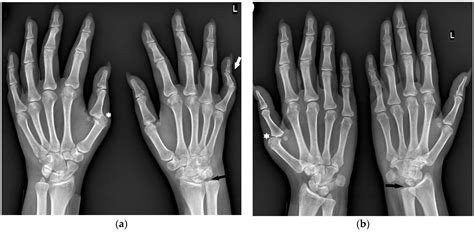

An MRI wrist joint scan is a non-invasive imaging technique that uses magnetic fields and radio waves to produce detailed images of the wrist. Unlike X-rays, which primarily show bones, MRI scans can visualize soft tissues such as ligaments, tendons, and cartilage. This makes MRI particularly useful for diagnosing conditions that affect these structures, such as fractures, ligament tears, and arthritis.

• Fractures: MRI can detect fractures that may not be visible on X-rays, especially in the early stages.

• Ligament and Tendon Injuries: Tears or strains in the ligaments and tendons can be clearly visualized with MRI.

• Arthritis: MRI can show the extent of cartilage damage and bone changes associated with arthritis.

• X-Rays: Useful for detecting bone fractures and certain types of arthritis.